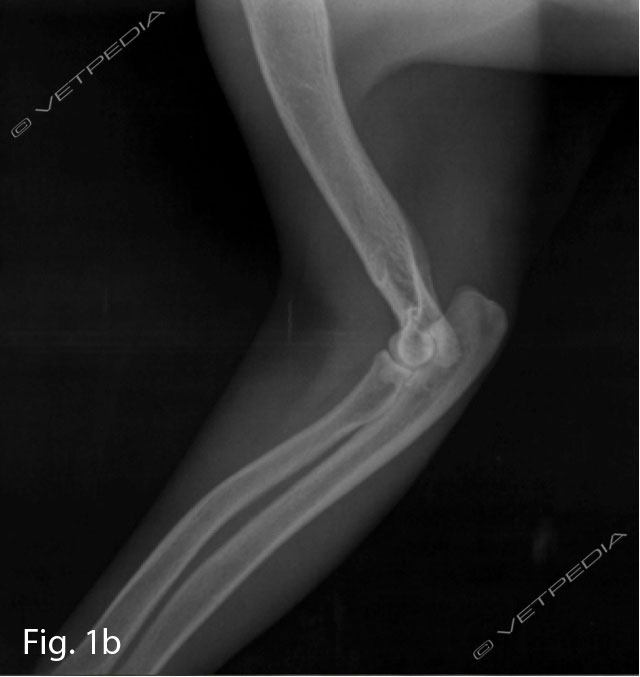

Studi hanno dimostrato che l’eccesso di energia può portare ad una crescita più rapida delle ossa lunghe e un’accelerazione del peso corporeo, che sovraccarica il sistema scheletrico. Un’alimentazione ad libitum può determinare l’insorgenzadelle seguenti patologie ortopediche: osteocondrosi, sindrome del radio curvo, alterazioni della conformazione dell’anca e sindrome di wobbler (Hedhamman et al. 1974) (Figg. 1a e 1b). Viceversa una carenza di energia può portare ad un rallentamento della crescita, ma con la ripresa di una corretta alimentazione il cane cresce più velocemente e più a lungo.